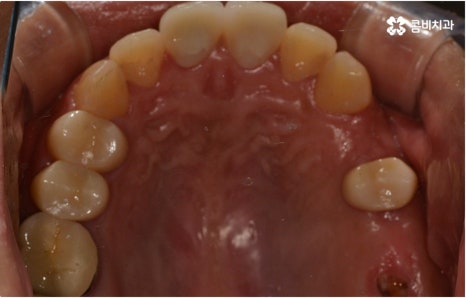

어떤 질병이든 이미 발병하고 나서 대응하는 것 보다는 평상시에 예방을 위해 힘쓰고 건강할 때 이를 유지하기 위해 노력하는 것이 좋다는 것은 당연한 얘기지만 또한 무심하게 넘길 수 있는 얘기이기 때문에 주의하실 필요가 있어요. 평상시 구강 건강을 지키는 방법 중 무엇보다 중요한 것은 내부 위생 관리에 신경 쓰는 것인데 그 이유는 충치 및 잇몸병 등 많은 구강 질환이 위생 관리가 불량한 데서 시작하기 때문이라고 할 수 있습니다. 위아래로, 즉 치아가 난 방향으로 너무 세지 않게 칫솔질을 해 주는 것과 치실 사용으로 꼼꼼하게 사이 사이 음식물 찌꺼기가 남아있지 않도록 해 주는 것, 그리고 평상시 칫솔질로 제거되지 않는 치석을 없애기 위해 주기적으로 명동치과 에 들러서 스케일링 치료를 받는 것을 추천드리고 있어요.

요즘은 많은 분들이 스케일링 치료 및 정기 검진의 중요성에 대해서 잘 인지하고 계시지만 예전에는 삼시세끼 식사 후 칫솔질을 잘 하는데 평상시에 왜 명동치과 에 정기적으로 방문해야 하는지 문의 주시는 분들도 많이 있었어요. 치태가 음식물 찌꺼기와 엉겨붙어 굳어서 치아 사이사이 또는 치아와 잇몸 사이에 치석으로 딱딱하게 자리잡게 되면 이것은 칫솔질로 떨어지지 않고 시간이 지날수록 점점 더 세균이 증식하는 온상이 되어 구강 질환을 일으킬 가능성이 높아지기 때문에 스케일링 치료로 치석을 물리적으로 떼어내 주실 필요가 있어요.

관리의 측면에서 교합이 맞지 않고 치열이 똑바르지 않으면 음식물 찌꺼기가 잘 끼고 잇몸이 붓기 쉽기 때문에 교정 치료가 필요할 수도 있습니다. 씹기가 어렵고 안면비대칭이나 턱관절 통증을 유발하는 등 심각한 부정교합의 경우 기능적으로도 필요하지만 약간 삐뚤어지거나 치아 사이가 벌어진 경우 심미적으로도 한 번쯤 교정 치료를 생각해 보셨을 텐데요, 가격이나 기간, 나이 등 여러 가지 부분이 신경쓰여서 막상 시작하기에 부감을 느끼고 계셨다면 먼저 명동치과 에 내원하셔서 자신에게 필요한 교정 치료가 어떤 것인지 알아보시면 좋을 거예요. 골격적인 원인이 크지 않고 정도가 심하지 않다면 환자분들의 상황에 따라 부분 교정으로 보다 짧고 간편하게 진행하는 경우도 있으니 3D CT 와 같이 정밀 검진 기계를 갖춘 치과에서 숙련된 의료진에게 검진 및 상담부터 받아보시길 권유드리고 있습니다.